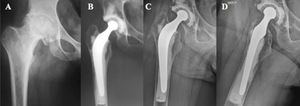

Además, observamos una asociación significativa entre revisión y el gradoC de la calidad del cementado según la clasificación de Barrack (fig. 3).

El análisis de supervivencia tras 16años de seguimiento mostró un porcentaje (84,2%) significativamente menor en los pacientes del grupo de reemplazos híbridos en comparación con los reemplazos cementados totales (89,9%) y no cementados (94,6%) (p<0,001) (fig. 4).

El odds-ratio observado en el grupoB respecto al riesgo de revisión contra los gruposA yC fue de 2,44 (IC95%: 1,00-5,96).

Sabemos que cierto grado de deficiencia en el manto del cemento alrededor de la prótesis podría llevar a un aflojamiento precoz34. Así pudimos observarlo en nuestro análisis, donde hubo una asociación estadísticamente significativa entre pacientes con gradoC (según la clasificación de Barrack) y fallo de fijación (p<0,01). Esto concuerda con lo reportado por Bardou-Jacquet35, donde observaron un mayor riesgo de fallo de fijación en pacientes con gradoC yD al compararlos con los gradoA yB.